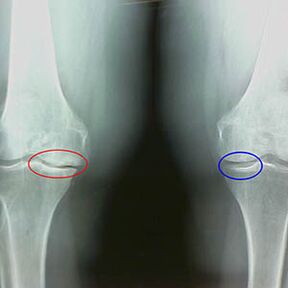

A térd arthrosis második szakaszának korai x -fázisának jellemzői:

- a sípcsonton az inter -írásbeli gumók hegyes szélei, ahol a kereszt alakú ligamentum rögzítve van;

- A közös rés szűkítése a mediális oldalon;

- A csontok condyles pontjai a medialis oldalakon, ritkábban oldalsóban - a valgus vagy a varior ízületi deformáció kialakulásától függően.

A Larsen második szakaszában Az ízületi rés több mint 50% -ával történő szűkítése jellemző, de ezt csak dinamikában vagy összehasonlításban lehet ellenőrizni egy eltérő ízületkel.

A röntgenfelvétel az osteofiták jelenlétét mutatja, a combcsont és a sípcsont csontok közötti tér változása, ami jelzi a porc elvesztését a térdben. Időnként a térdízületek x -súrja a porc kopásának jelentős jeleit mutatja, de a betegek nem szenvednek jelentős fájdalmat.Éppen ellenkezőleg, az első szakasz artrózisa megzavarhatja a térd funkciójátmivel a fájdalom oka a hipotonikus izmok.